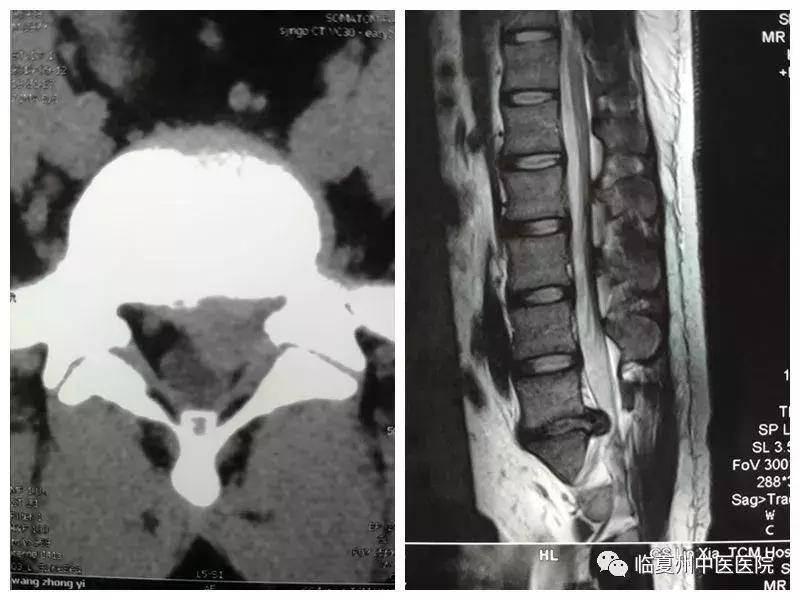

患者黄某,男性,29岁,1年前因腰背部疼痛伴左下肢麻木,在当地医院查腰椎MR及CT,被诊断为“腰椎间盘突出症”,前往省内外多家医院住院治疗,症状无明显缓解,1周前腰痛加重,左下肢后侧及足底麻痛,左小腿肌肉明显萎缩,不能平卧及行走,几经辗转,来我院就诊,平车推入院。张卫东主任医师询问患者病史,进行了详细查体,审阅影像学资料,认为患者诊断明确,系腰5骶1节段后外侧突出,神经根受压明显,经保守治疗无效,手术指征明确。特邀王永平院长、主任医师会诊,经讨论,认为患者为青年男性,肥胖,传统手术创伤大、术后康复时间长、术后易出现腰椎不稳等并发症,最佳手术方式为脊椎内镜下椎间盘髓核摘除术。患者术后麻醉过后腰痛消失,左下肢及足底麻痛完全消失,腰部及下肢活动恢复正常。

图为术前影像资料